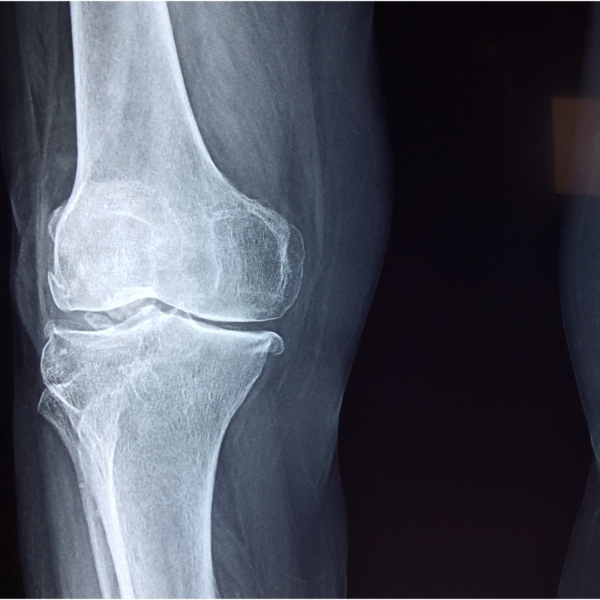

Arthritis? That’s just right…

Sitting too long can lead to neck pain, back pain, even knee pain. Great… They found arthritis. Many people who are diagnosed with…